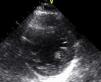

A paciente teve alta clinicamente estável. Atualmente, encontra-se bem, sem sinais clínicos de ICC. Encontra-se dependente da função pacing do CDI de dupla câmara, sem choques detetados. O rastreio de familiares diretos revelou ECG normais, com os ecocardiogramas dos seus filhos a revelarem imagens sugestivas de não compactação miocárdica inferior e lateral (Figura 6) (com o ECG de alta resolução dos mesmos a não revelar alterações). Aguarda-se atualmente o estudo genético da paciente.